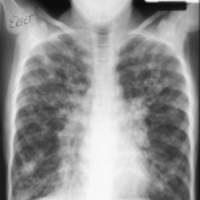

Students investigate cystic fibrosis by comparing the chest X-rays of a healthy individual and an individual with cystic fibrosis. Students read information on cystic fibrosis and work together to determine the genetic causes of this specific disorder.

Pass out Student Handout 1 or show the two X-ray images to the class using a projector.

Ask students to examine the two X-rays and explain the differences. They will record their responses in the explanation boxes provided on the handout or in their notebooks.

Briefly have students share out their responses.